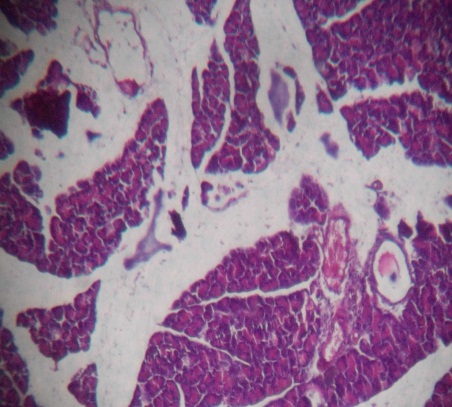

Histopathology slides of Ankle joint of Rasa Mezhugu treated rats showed normal synovial membrane, the anterior articular region with articular cartilage by the presence of no flocculation on the articular surface normal cellular organization; and the articular cavity has no synovial infiltration and the formation of pannus [14, 16]. The pictures show nearly normal histological features with almost intact bone and cartilage, in addition to normal joint space (fig. 4-7).

The bone marrow of Rasa Mezhugu treated rats (high/low/Middle dose) found within the central cavities of with hematopoietic tissue islands and adipose cells surrounded by vascular sinuses interspersed within a meshwork of bone (fig. 8-10). The cerebrum showed the absence of neuronal degeneration, edema and gliosis (fig. 11-13). The Cardiac muscle revealed normal appearances of the centrally arranged nucleus, connective tissue with distinct cardiac muscle fibers were well arranged (fig. 14-16). The kidney shows no glomerular or vascular injury the bowman's capsule with distinct polymorphonuclear cell nuclei with normal cells of renal cortex (fig. 17-19). The liver cells showed the normal microscopic architecture of the liver with hexagonal lobules and acini with the distinct central vein, portal triad, portal vein and hepatic artery with parenchyma cells (fig. 20-22). The lungs photos revealed that normal cytoarchitectural with predominant smooth muscle layer of the bronchi with enlargement of the alveoli and the alveoli sacs (fig. 23-25). The pancreas with normal acinar cells arranged in lobules with prominent nuclei. The islet cells are embedded within the acinar cells and surrounded by a fine capsule with normal histological structure (fig. 26-28). The spleen showed no changes congestion, hemorrhage, edema, and erosions the cells are a clear and proper arrangement (fig. 29-31). Photomicrograph of stomach mucosal layer has shown normal cells with distinct mucosa, submucosa, muscle layers and serosal layers showing normal architecture (fig. 32-34). The tests of rat’s revealed normal architecture with normal germinal epithelium, fully mature sperms filled the lumen of seminiferous tubules with tubular epithelium cells, absences of vascular congestion/interstitial edema and degenerated cells (fig. 35-37).

| Fig. 4: Histopathology slides-Ankle joint of the Indomethacin treated animals | Fig. 5: Histopathology slides-Ankle joint of the Rasa Mezhugu treated animals |

| Fig. 6: Histopathology slide photos of Rasa Mezhugu-High dose treated animals’ bone | Fig. 7: Histopathology slide photos of Rasa Mezhugu-Low dose treated animals’ bone |